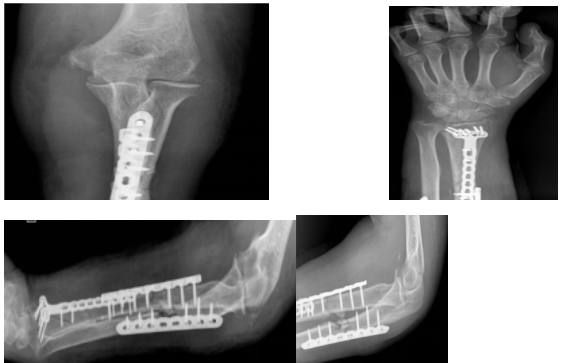

骨科开展开放性孟氏骨折

伴桡骨多段骨折切开复位内固定术新技术

手术顺利,历时1小时30分,术后复查手术植入钢板固定良好,为后期前臂功能康复或功能重建奠定了良好基础。

2023年2月27日凌晨01时34分,州人民医院骨科病区,当值医生黄孝明主治医师正在急诊收治一例58岁复合伤藏族女性患者,患者系阿坝县洛尔达乡人,13小时前因车祸致左前臂肿痛、畸形、流血、功能障碍,伴头痛、胸痛、左耳道流液。入科时患者烦躁不安,呈休克状,畸形的左前臂连同衣袖夹板敷料包扎、外置支具固定,敷料全层被血液浸透,检查见左前臂中份背侧一约5cm横向伤口,前内侧一约12cm纵向伤口,活动性出血,肢端冰凉,桡动脉无法扪及,左手感觉、手腕运动明显减退。急诊CT显示:多发脑挫裂伤(右顶叶、额叶及颞叶)、创伤性蛛网膜下腔出血、左侧乳突骨折;左侧多支肋骨骨折(第7—10);腹腔未见明显异常;左尺桡骨多段骨折、左桡骨头脱位。

州人民医院骨科有着丰富的急危重症患者救治经验,面对该复合伤重症患者,黄孝明主治医师第一时间请示科主任吴俊一,启动抢救程序,快速补液扩容、输血等抗休克治疗;同时请神经外科等多学科会诊评估,颅脑等部位暂无手术指征。患者左前臂渗血不止,生命体征相对平稳后,黄孝明主治医师当即安排紧急手术,按照损伤控制手术原理,一期手术行左尺骨开放性骨折复位克氏针内固定术+血管、神经、肌腱探查修复、清创缝合术。